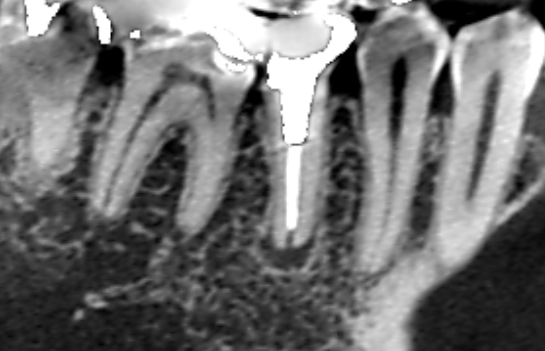

初診時のCT画像です。

赤い矢印の先に膿の影がみられます。

根管充填が根の先まで足りず、細菌が繁殖できる空間ができているために膿んでいる可能性があります(青い矢印の先)。